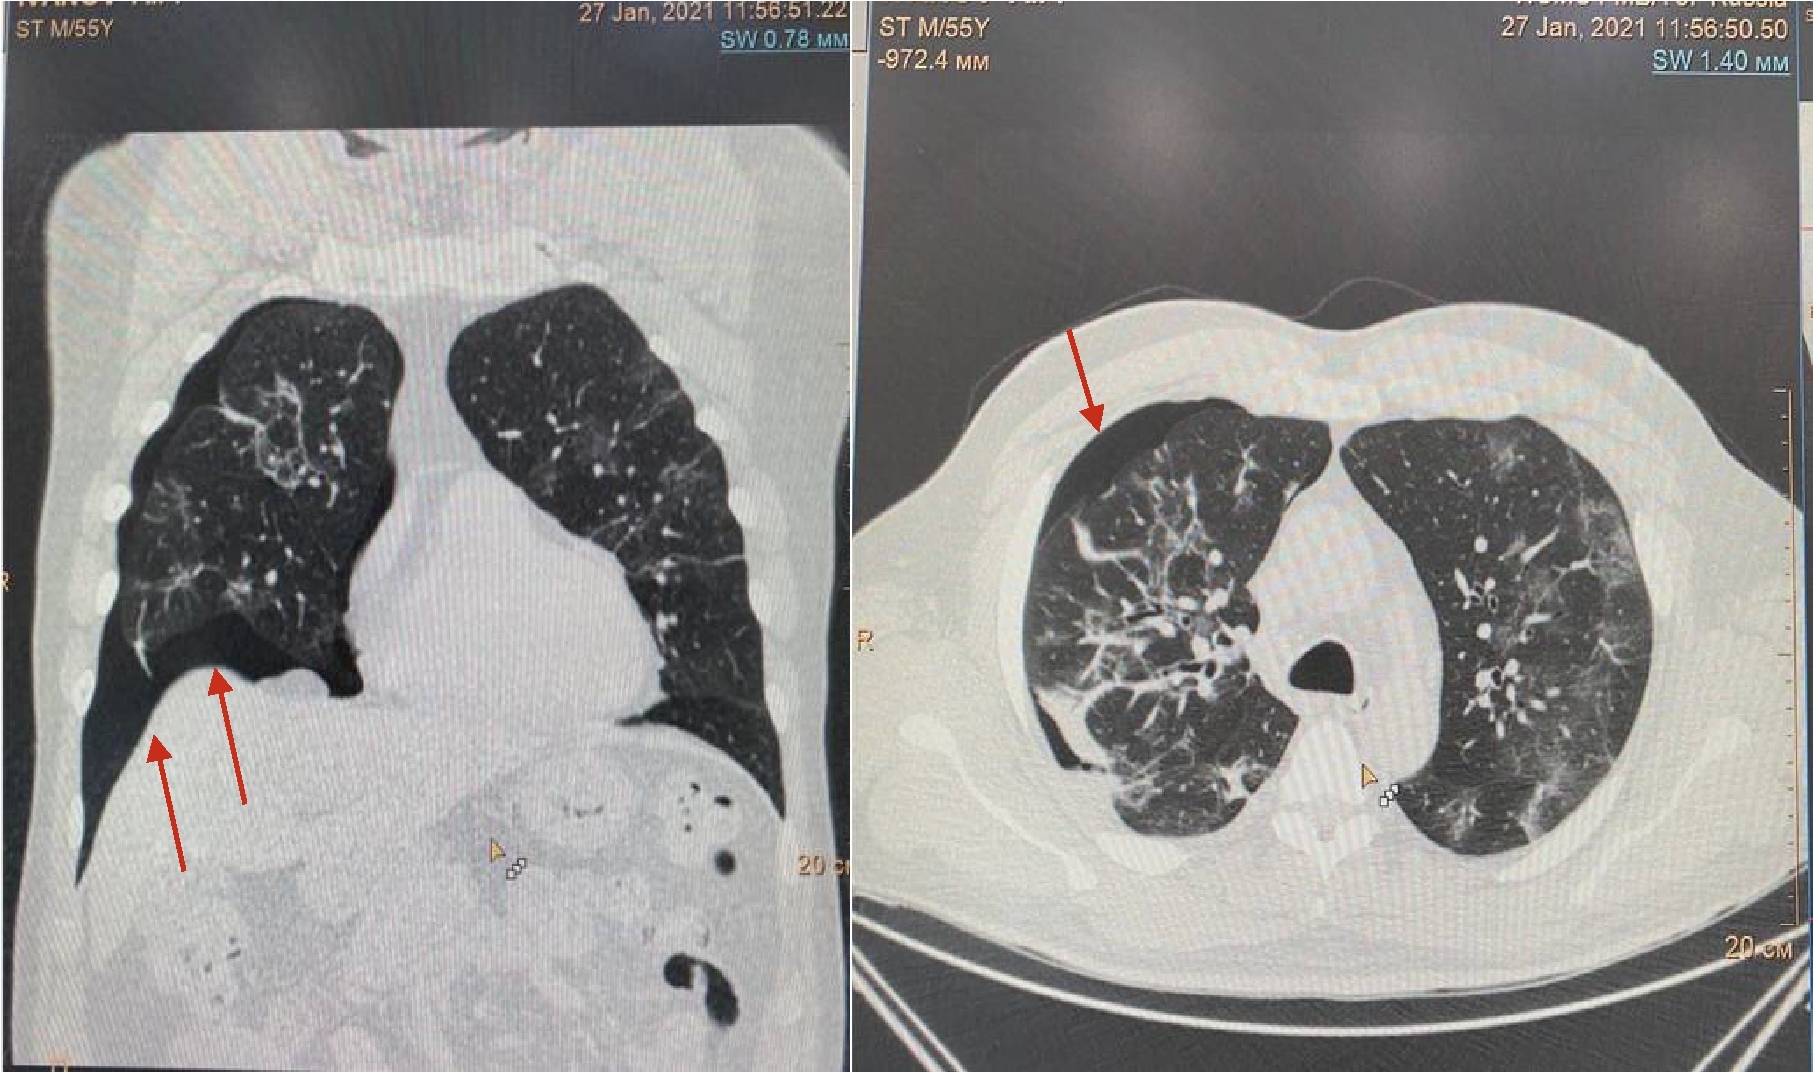

На 16 сутки госпитализации пациент начал жаловаться на резкое усиление одышки даже в покое, невозможность находиться в прон-позиции. МСКТ органов грудной клетки обнаружила уменьшение объема поражения легких до 30%, также был впервые выявлен спонтанный средний правосторонний пневмоторакс (рис. 3).

Рисунок 3. МСКТ органов грудной клетки – признаки двусторонней полисегментарной интерстициальной пневмонии (объем поражения 30%, КТ-2). Средний правосторонний пневмоторакс (красные стрелки).

Появлению данного осложнения не предшествовали какие-либо инвазивные манипуляции в области дыхательных путей, пищевода, пациент не находился ИВЛ. Однако возникновение ПТ коррелирует усугублением дыхательной недостаточности, снижением SpO2 (рис. 4) с пиком ЛДГ (до 397 ед/л), уровень которого прогрессивно возрастал на протяжении всего лечения (рис. 5).